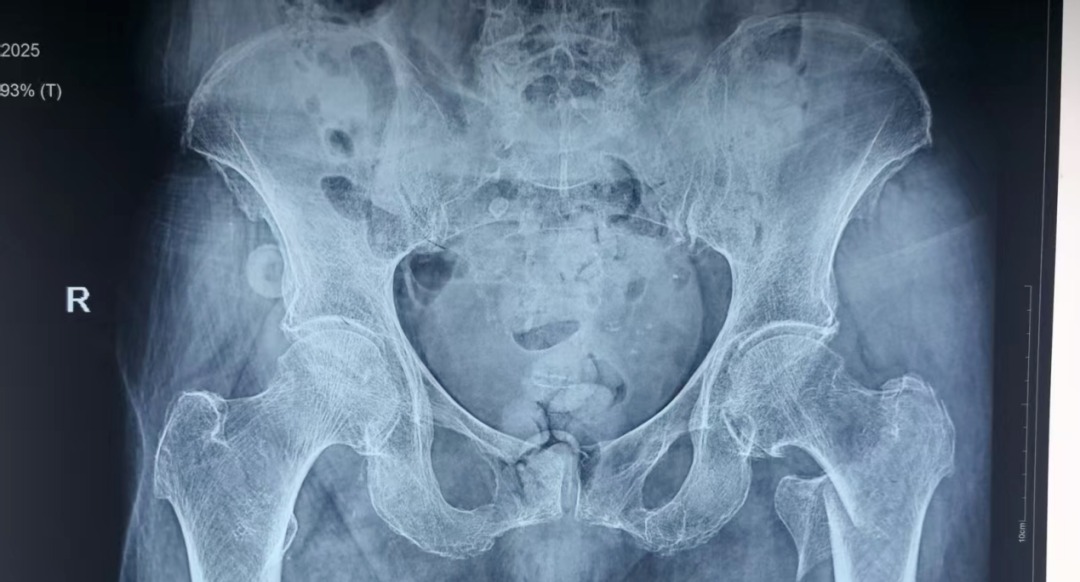

近日,患者李某某在即将迎来自己103岁生日时,不慎在家摔倒导致左髋关节疼痛伴活动受限,就诊于当地医院诊断为左侧股骨转子间骨折,因患者为超高龄老人,当地医院考虑手术风险大,建议转诊上级医院进行治疗。患者家属遂联系120转诊至51风流

为防止坠积性肺炎、褥疮、深静脉血栓等并发症发生,杨自权主任团队在患者入院后,积极完善术前准备,经过医务处的组织和血管外科、麻醉科、康复科等多学科的MDT合作,手术时间定于患者入院第三天。2022年,美国AAOS(美国骨科医师协会)指南强烈推荐老年股骨转子间骨折(稳定或不稳定)采用髓内钉内固定。因此,杨自权主任团队拟行股骨转子间骨折闭合复位髓内钉内固定微创手术。

手术当日,杨自权主任团队借助丰富的手术经验,术前在牵引床、G臂辅助下迅速给予患者闭合复位骨折断端,结合经典的“2-1-1”微创手术切口实施手术,手术过程顺利,G臂透视可见骨折复位满意,髓内钉位置满意。术后患者顺利出院,安返家中。